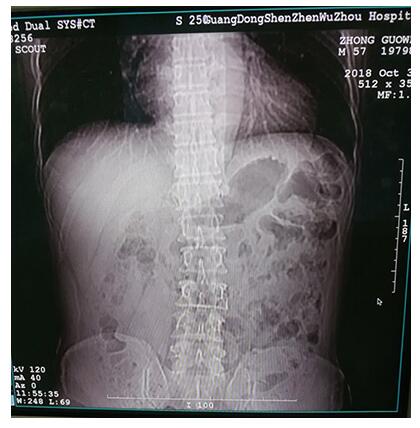

10月5日,家住龙岗的钟先生,由儿子驱车送来五洲医院进行诊治,雷作志主任接诊后,先安排钟先生去拍片检查,发现钟先生除了患有中风后遗症带来的偏瘫,还有腰椎间盘突出症。考虑到钟先生的特殊情况,雷主任决定采取小针刀疗法,再以手法复位为辅,进行治疗。每周治疗一次,对其肩部、肘部、腰部等部位进行治疗。

钟先生腰部脊椎明显侧弯突出